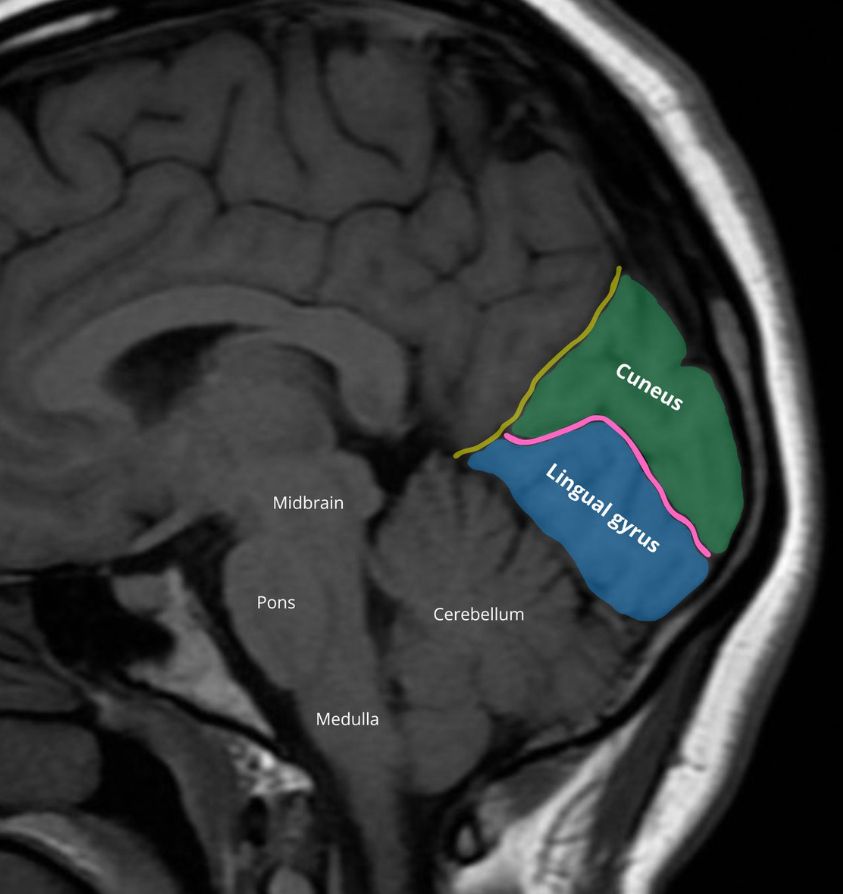

The Neuroanatomy Post 🗞️

Parieto-occipital fissure (yellow)/calcarine sulcus (pink)

Primary visual cortex lies along the calcarine sulcus.

Cuneus (green) is the site of basic visual processing.

Lingual gyrus (blue) - face & landmark perception and recognition and visual memory.

#Radiology